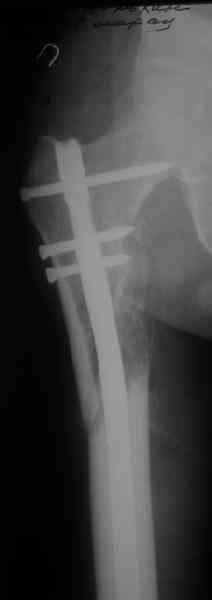

> денамизация - февраль 2006. ( 3 и 4 снимки) на сегодняшний день (снимок 5) беспокоит боли в тбс...

Однозначно: удалить, рассверлить, перештифтовать более толстым гвоздем. ЭТОТ 9 мм будет? Возьмите 12-14.

Дистально обязательно два винта! Проксимально можно один динамический. Больной будет счастлив на следующий же день!

Учитывая точку введения - верхушка б\вертела - что бы исправить варус взял бы соответствующий гвоздь: длинную Гамму или PFN или Recon

Судя по уровню перелома, винты в шейку избыточны, подойдет и диафизарный гвоздь. Все, что нужно, это тиски и труба. Загнуть сразу ниже отверстий градусов на 8-10, и вся недолга. Последние годы у нас это рутинная практика. Предызогнутые еще с завода гвозди неудобны тем, что они уже правый-левый.

Согласен, что 3,5 см укорочение этим снимкам не соответствует, за счет перелома и деформации - 1,5 см от силы. То есть либо ошибка измерения, либо приводящая контрактура, либо укорочение за счет другого отдела.

Согласен, что закрытый реостеосинтез с рассверливанием и коррекцией оси - это то, что надо. Мы бы ввели в центральный отломок статических 2-3 винта, и один динамический винт в дистальном отломке.